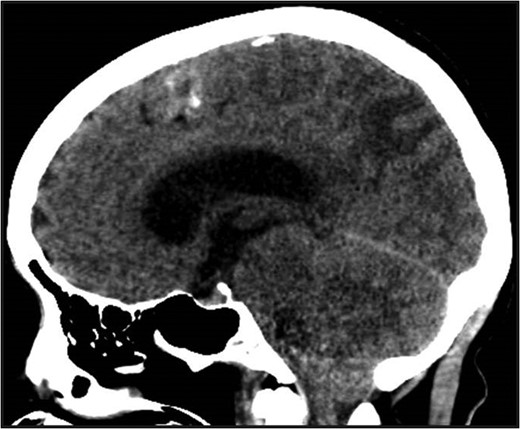

MRI brain 3 months post-diagnosis, Axial T2 sequence. Normalization of imaging with resolution of vasogenic edema and pneumocephalus.